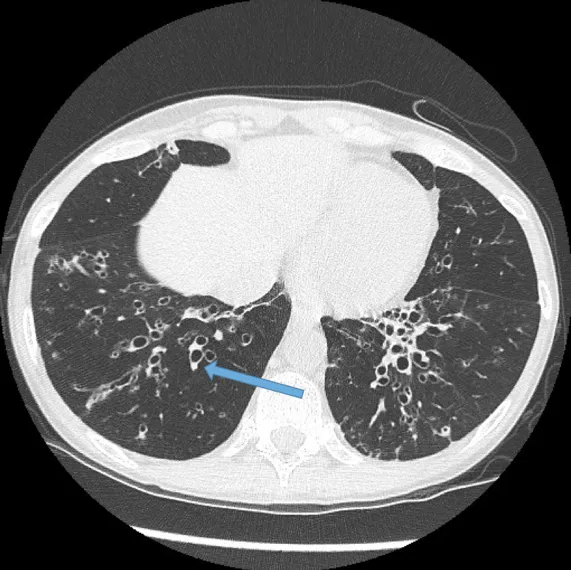

Diagnosis: High-resolution CT (HRCT) is the gold standard imaging test.

- Key HRCT signs: ↑ broncho-arterial ratio >1 ("signet ring" sign), and lack of airway tapering ("tram tracks").

- High-resolution CT (HRCT) is the diagnostic gold standard, revealing "tram tracks" and the "signet ring" sign.